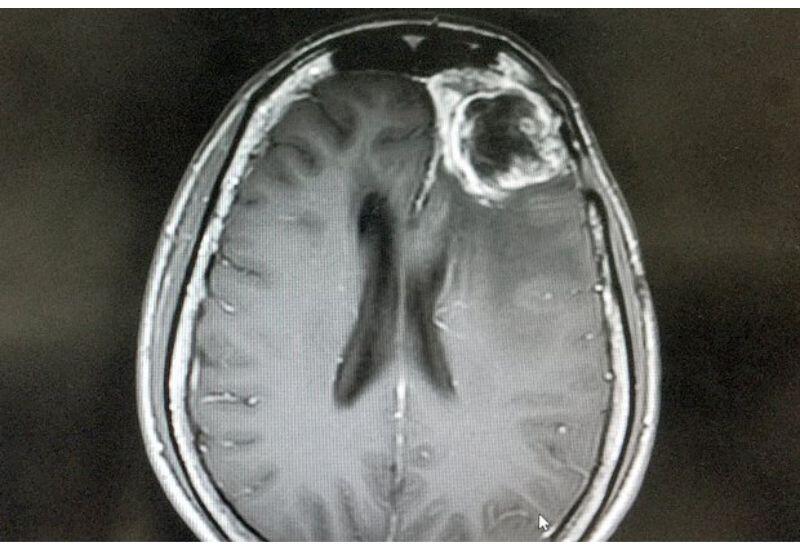

Найден способ замедлить рост агрессивного рака

Глиобластома, один из самых агрессивных видов рака мозга, использует глюкозу иначе, чем здоровые клетки. Исследование, опубликованное в Nature, показало: вместо получения энергии и синтеза нейромедиаторов опухоль перенастраивает сахарный обмен, превращая глюкозу в строительные блоки ДНК и РНК. Это ускоряет деление и распространение раковых клеток, передает Day.Az со ссылкой на Lenta.ru.